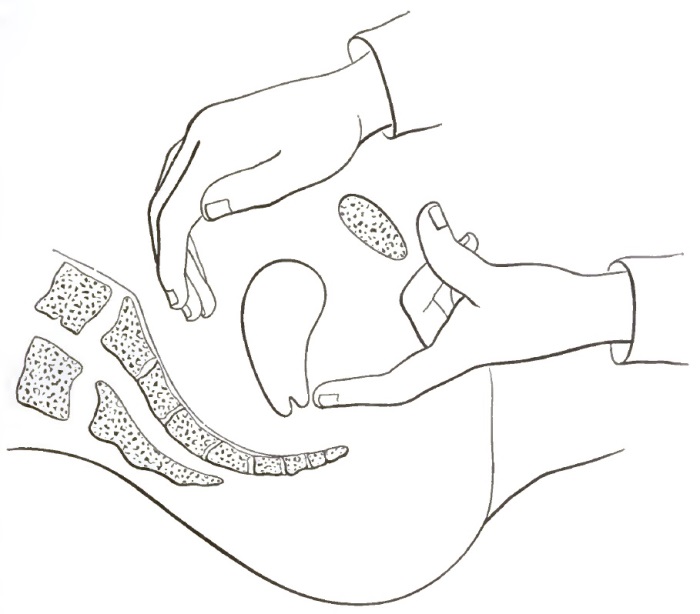

| 16. | COMMENCING REPOSITION OF THE RETROVERTED OR RETROFLEXED UTERUS BY CONJOINED MANIPULATION |